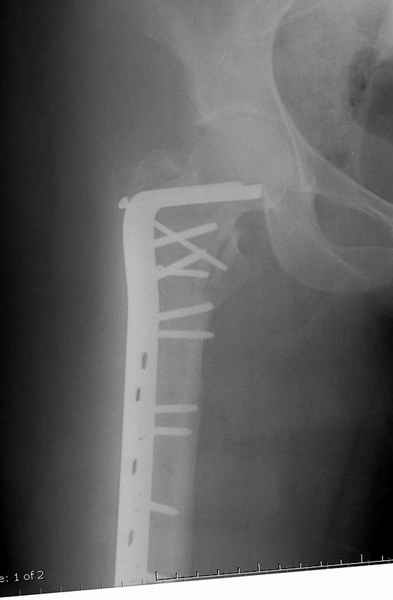

Postop Blade Fixation

Для молодых больных выбрал бы тактику fixed angled device 95 degree Blade Plate, техника непрямого метода репозиции, который описал в своей книге Jeff Mast, Planning and Reduction Technique in Fracture Surgery ( method of Inderect Reduction), репозиция и фиксация происходит за счет фиксации головки бедра к femoral shaft с помощью пластины, а что в середине должны репонироваться без больших усилии и без разрушения мягкотканого соединения c медиальной стороны.

Пластина дает свободу:

Valgus-varus; extention- flexion, зависит только от образования канала для blade на головке.

Ap pelvis Rt sub-intra trochanteric Fracture, AP Rt hip, Postop Blade Fixation